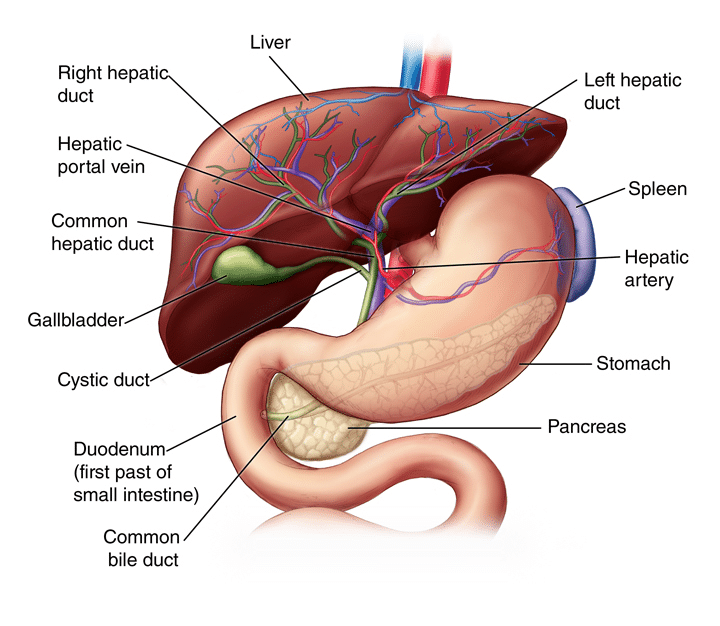

Covid-19: Η δρ Jawaher Alharthi, από το Ινστιτούτο Westmead και την ιατρική έρευνα του Πανεπιστημίου του Σίδνεϊ της Αυστραλίας, και οι συνεργάτες της ανακάλυψαν πώς η COVID-19 αυξάνει τον κίνδυνο λιπώδους ηπατικής νόσου και πώς η τελευταία αυξάνει τη σοβαρότητα της COVID-19, βοηθώντας στην ανάπτυξη πιθανών θεραπειών για τους ασθενείς αυτούς. Η σχετιζόμενη με τη μεταβολική δυσλειτουργία λιπώδης νόσος του ήπατος (MAFLD) επηρεάζει έναν στους τέσσερις ενήλικες και σχεδόν ένα στα δέκα παιδιά παγκοσμίως. Σε παγκόσμιο επίπεδο, η λιπώδης νόσος του ήπατος MAFLD είναι το συχνότερο είδος χρόνιας ηπατικής νόσου.

Η ηπατική νόσος είναι ένας σιωπηλός δολοφόνος. Οι περισσότεροι άνθρωποι δεν γνωρίζουν ότι έχουν ηπατικό πρόβλημα έως ότου αυτό προχωρήσει και αναπτύξουν ουλές στο ήπαρ, κίρρωση του ήπατος και, σε σοβαρές περιπτώσεις, ηπατική ανεπάρκεια και θανατηφόρο καρκίνο. Οι επιπλοκές της, ωστόσο, δεν περιορίζονται στην ηπατική νόσο. Συνδέεται στενά με διάφορες άλλες καρδιομεταβολικές παθήσεις, όπως ο διαβήτης τύπου 2 και οι καρδιαγγειακές παθήσεις. Ως απάντηση στην COVID-19, ο ξενιστής (άνθρωπος) αναπτύσσει μια ανοσολογική απάντηση, η λεπτή ισορροπία της οποίας καθορίζει την πορεία της νόσου. Η σοβαρή COVID-19 σχετίζεται με επιδεινωμένες ανοσολογικές και υπερφλεγμονώδεις αποκρίσεις και τα φλεγμονώδη μακροφάγα μπορούν να προκαλέσουν καταιγίδα κυτοκινών που οδηγεί σε ιστική βλάβη. Μια νέα μελέτη από ερευνητές του Ινστιτούτου Ιατρικής Έρευνας Westmead του Πανεπιστημίου του Σίδνεϊ ανακάλυψε πώς η COVID-19 αυξάνει τον κίνδυνο λιπώδους ηπατικής νόσου και πώς το τελευταίο αυξάνει τη σοβαρότητα της COVID-19, βοηθώντας στην ανάπτυξη πιθανών θεραπειών για τους ασθενείς αυτούς.

Ο Δρ Jawaher Alharthi, πρώτος συγγραφέας της εργασίας αυτής, δήλωσε: “Η σχέση μεταξύ της λιπώδους νόσου του ήπατος και της COVID-19 θεωρείται λίγο μυστήριο, καθώς δεν γνωρίζουμε πώς και γιατί οι δύο ασθένειες αυξάνουν τον κίνδυνο η μία της άλλης. Η ερευνητική μας ομάδα με επικεφαλής τον καθηγητή Mohammed Eslam διεξήγαγε μια μεγάλη και λεπτομερή γενετική και μοριακή μελέτη και εντόπισε ότι το γονίδιο που ονομάζεται MBOAT7 σχετίζεται με τη σοβαρότητα τόσο της λιπώδους νόσου του ήπατος MAFLD όσο και της COVID-19”. “Αυτό το γονίδιο, παίζει σημαντικό ρόλο στη ρύθμιση των ανοσολογικών και φλεγμονωδών αποκρίσεων κατά της COVID-19. Μια διαταραχή στη δραστηριότητα του γονιδίου MBOAT7 θα μπορούσε να αυξήσει τις πιθανότητες αύξησης της παραγωγής κυτταροκινών και της βλάβης των ιστών και της ηπατικής νόσου”, δήλωσε ο Δρ Alharthi. Το επιγονιδίωμα είναι ένα σύνολο δεικτών που καθορίζει όχι μόνο τη γονιδιακή έκφραση, αλλά και τα ίδια τα γονίδια και επηρεάζεται από το περιβάλλον, τη διατροφή και τις ορμόνες. “Είναι ενδιαφέρον ότι εντοπίσαμε επίσης ότι η διακοπή του MBOAT7 μπορεί να “προ-προγραμματίσει” το επιγονιδίωμα των κυττάρων και να τα προετοιμάσει ώστε να ανταποκριθούν έντονα ακόμη και σε μια ασθενή διέγερση κατά της COVID-19 που τελικά αυξάνει τη βλάβη των ιστών”.